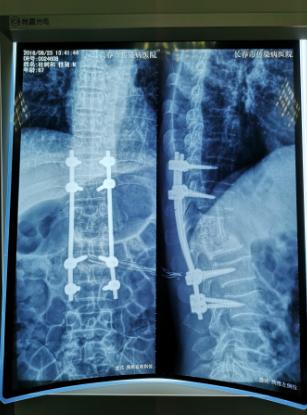

经过检查,罗坚主任凭着丰富的临床经验初步认为王大爷患的是胸椎结核伴脊髓压迫症,那么是什么原因造成的?通过脊柱磁共振检查,罗主任发现王大爷患胸椎脊髓压迫的元凶正是“骨结核”。王大爷胸椎骨7-11节被结核杆菌严重侵蚀,在重体力活后,胸椎脊髓神经受到压迫,最终导致下肢瘫痪。同时患者双肺结核伴左上叶不张,左侧胸腔大量积液。如果等待双肺结核治愈,需时日很长,脊髓的受压如果不能及时解除,导致脊髓变性,那么瘫痪就难以恢复了,在积极治疗肺结核胸腔积液引流,罗坚主任为王大爷尽快安排实施手术。

手术过程中,病人腰大肌脓肿巨大,病椎破坏重游离死骨多,结核物质使脊髓严重受压,既要侧前方减压清除病灶,又要完成后凸畸形的矫正,再由于王大爷年龄较大、体质差,风险高,对技术与手术期管理都是很大的挑战。

罗坚、陈松峰和任重三位医师组成的团队实施手术。罗坚主任凭借其多年外科生涯中大量胸椎结核手术所积累的丰富经验,在脊柱侧前方减压,病灶清除、植骨和后凸畸形矫正胸膜外操作。手术按计划顺利完成,而辗转数家医院的“求医记”终于告一段落,在外等候的家人听到手术成功的消息后喜极而泣。